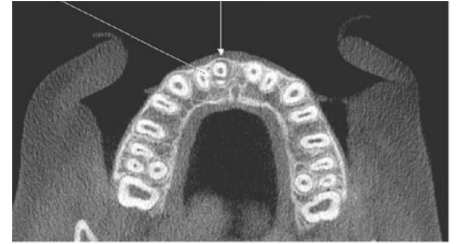

Identifique na radiografia o elemento dental fraturado: